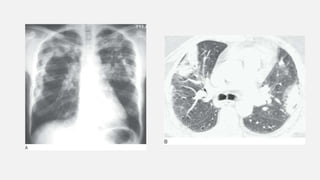

• #27 Perihilar “bat-wing” consolidation in pulmonary edema. A: Chest radiograph shows a distinct perihilar predominance of consolidation. The heart is enlarged. B: CT shows sparing of the lung periphery.

• #29 Peripheral subpleural (reverse bat-wing) consolidation. A: Chest radiograph in a patient with chronic eosinophilic pneumonia shows areas of consolidation in the subpleural lung. The perihilar regions are spared. B: CT in a patient with OP shows patchy areas of consolidation in the subpleural lung.